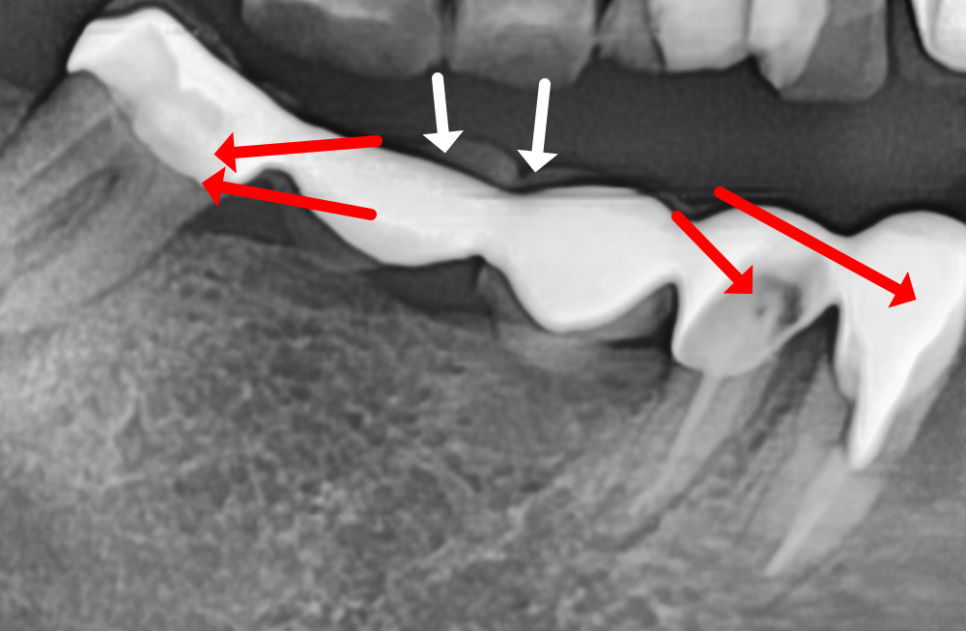

이 환자분은 오른쪽 아래,

무려 5개의 치아를 연결한

긴 브릿지가 통째로 빠져서 오셨는데요.

250507

무엇보다 브릿지를 지탱하던

앞 치아(#43)는

과도한 힘을 버티지 못하고

치아 반쪽이 깨져 있었습니다.

맨 끝 치아(#47) 역시 뿌리 끝에

고름주머니가 크게 잡혀 있었죠.